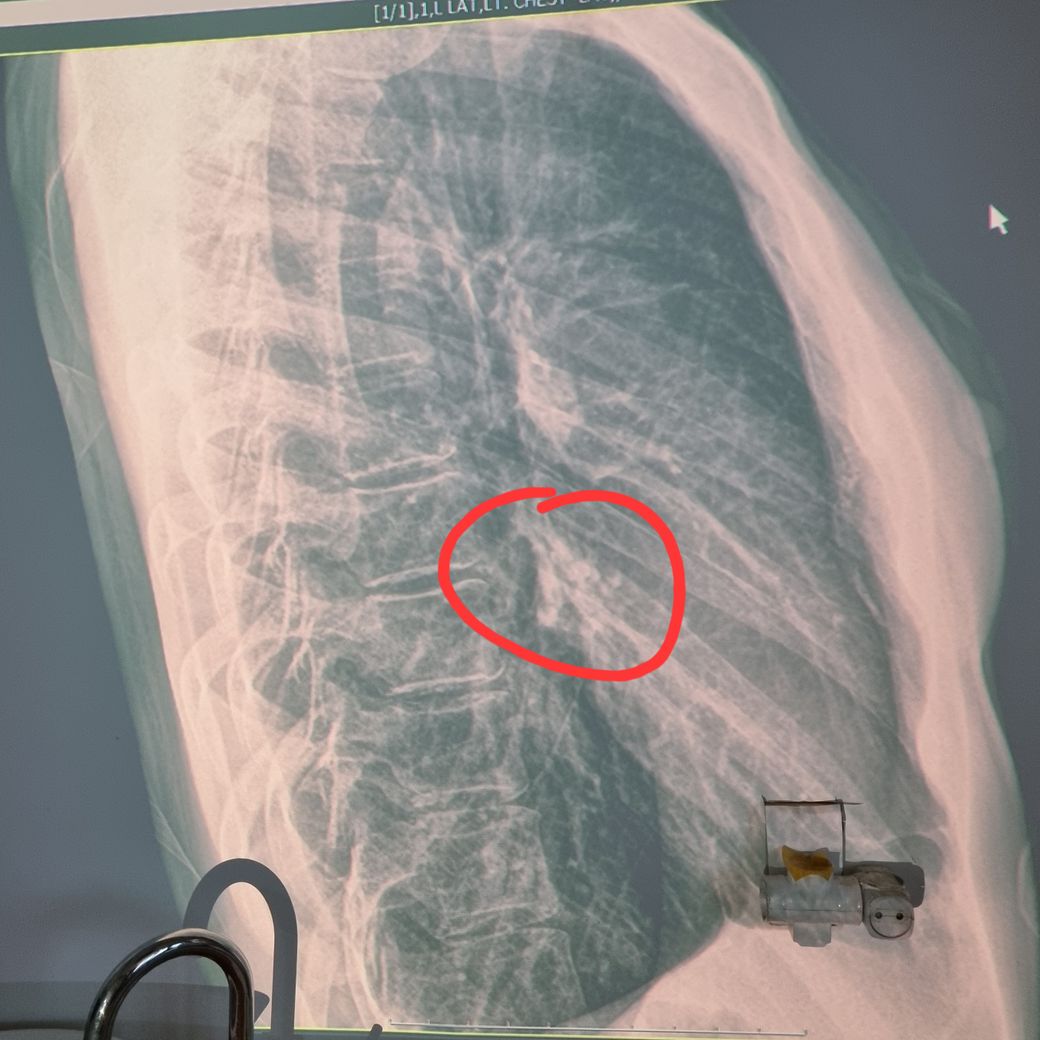

내과에 페 엑스레이를 찍었는데요

과거에 폐렴을 앓았던 흔적이 있다며 지금 항생제 투여를 열흘간 하자고 합니다

현재 증상은 숨 들여마실때에 왼쪽 특정 가슴부분에서 두둑 하는 느낌? 들어서 기흉 의심했으니 기흉은 아니라는데요..

• 1번 째 사진